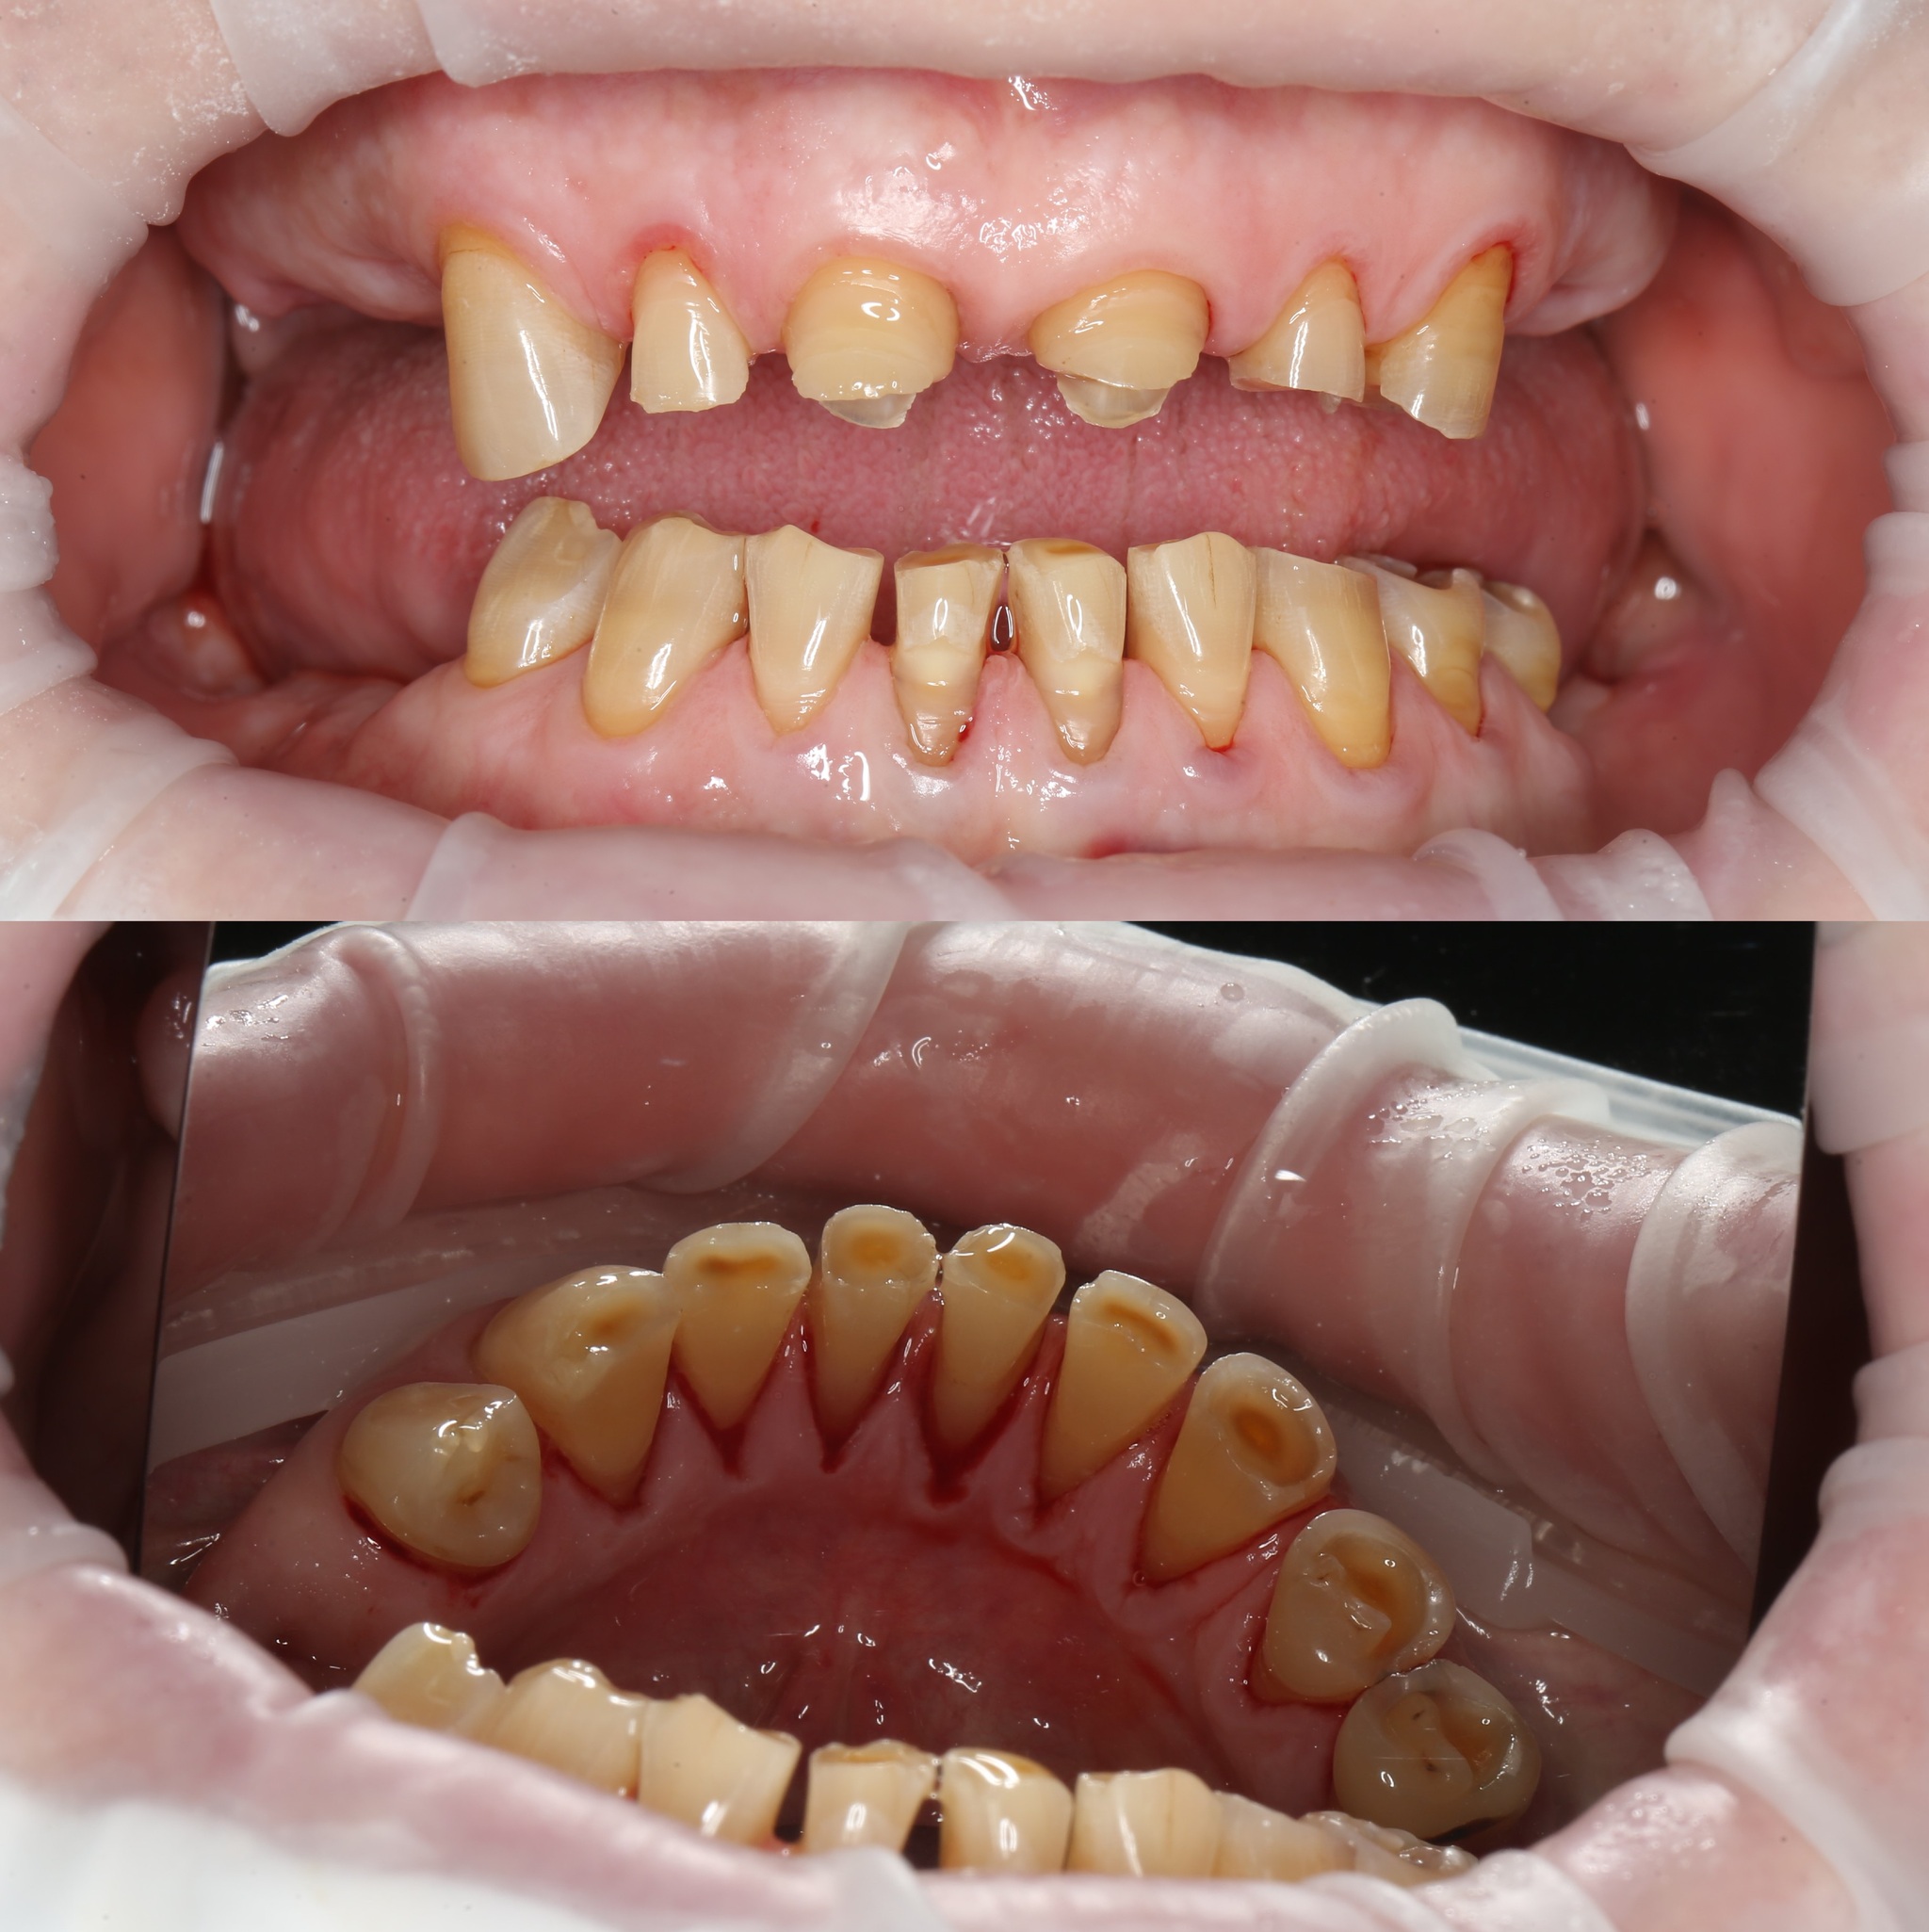

Первым делом была проведена профессиональная гигиена полости рта. Соглашусь, ее нужно было сделать еще до удаления зубов, но мы не укладывались в сроки.

Отмечается пигментированный зубной налет и отложения солей камней в области зубов на нижней челюсти с язычной стороны.

После чистки: